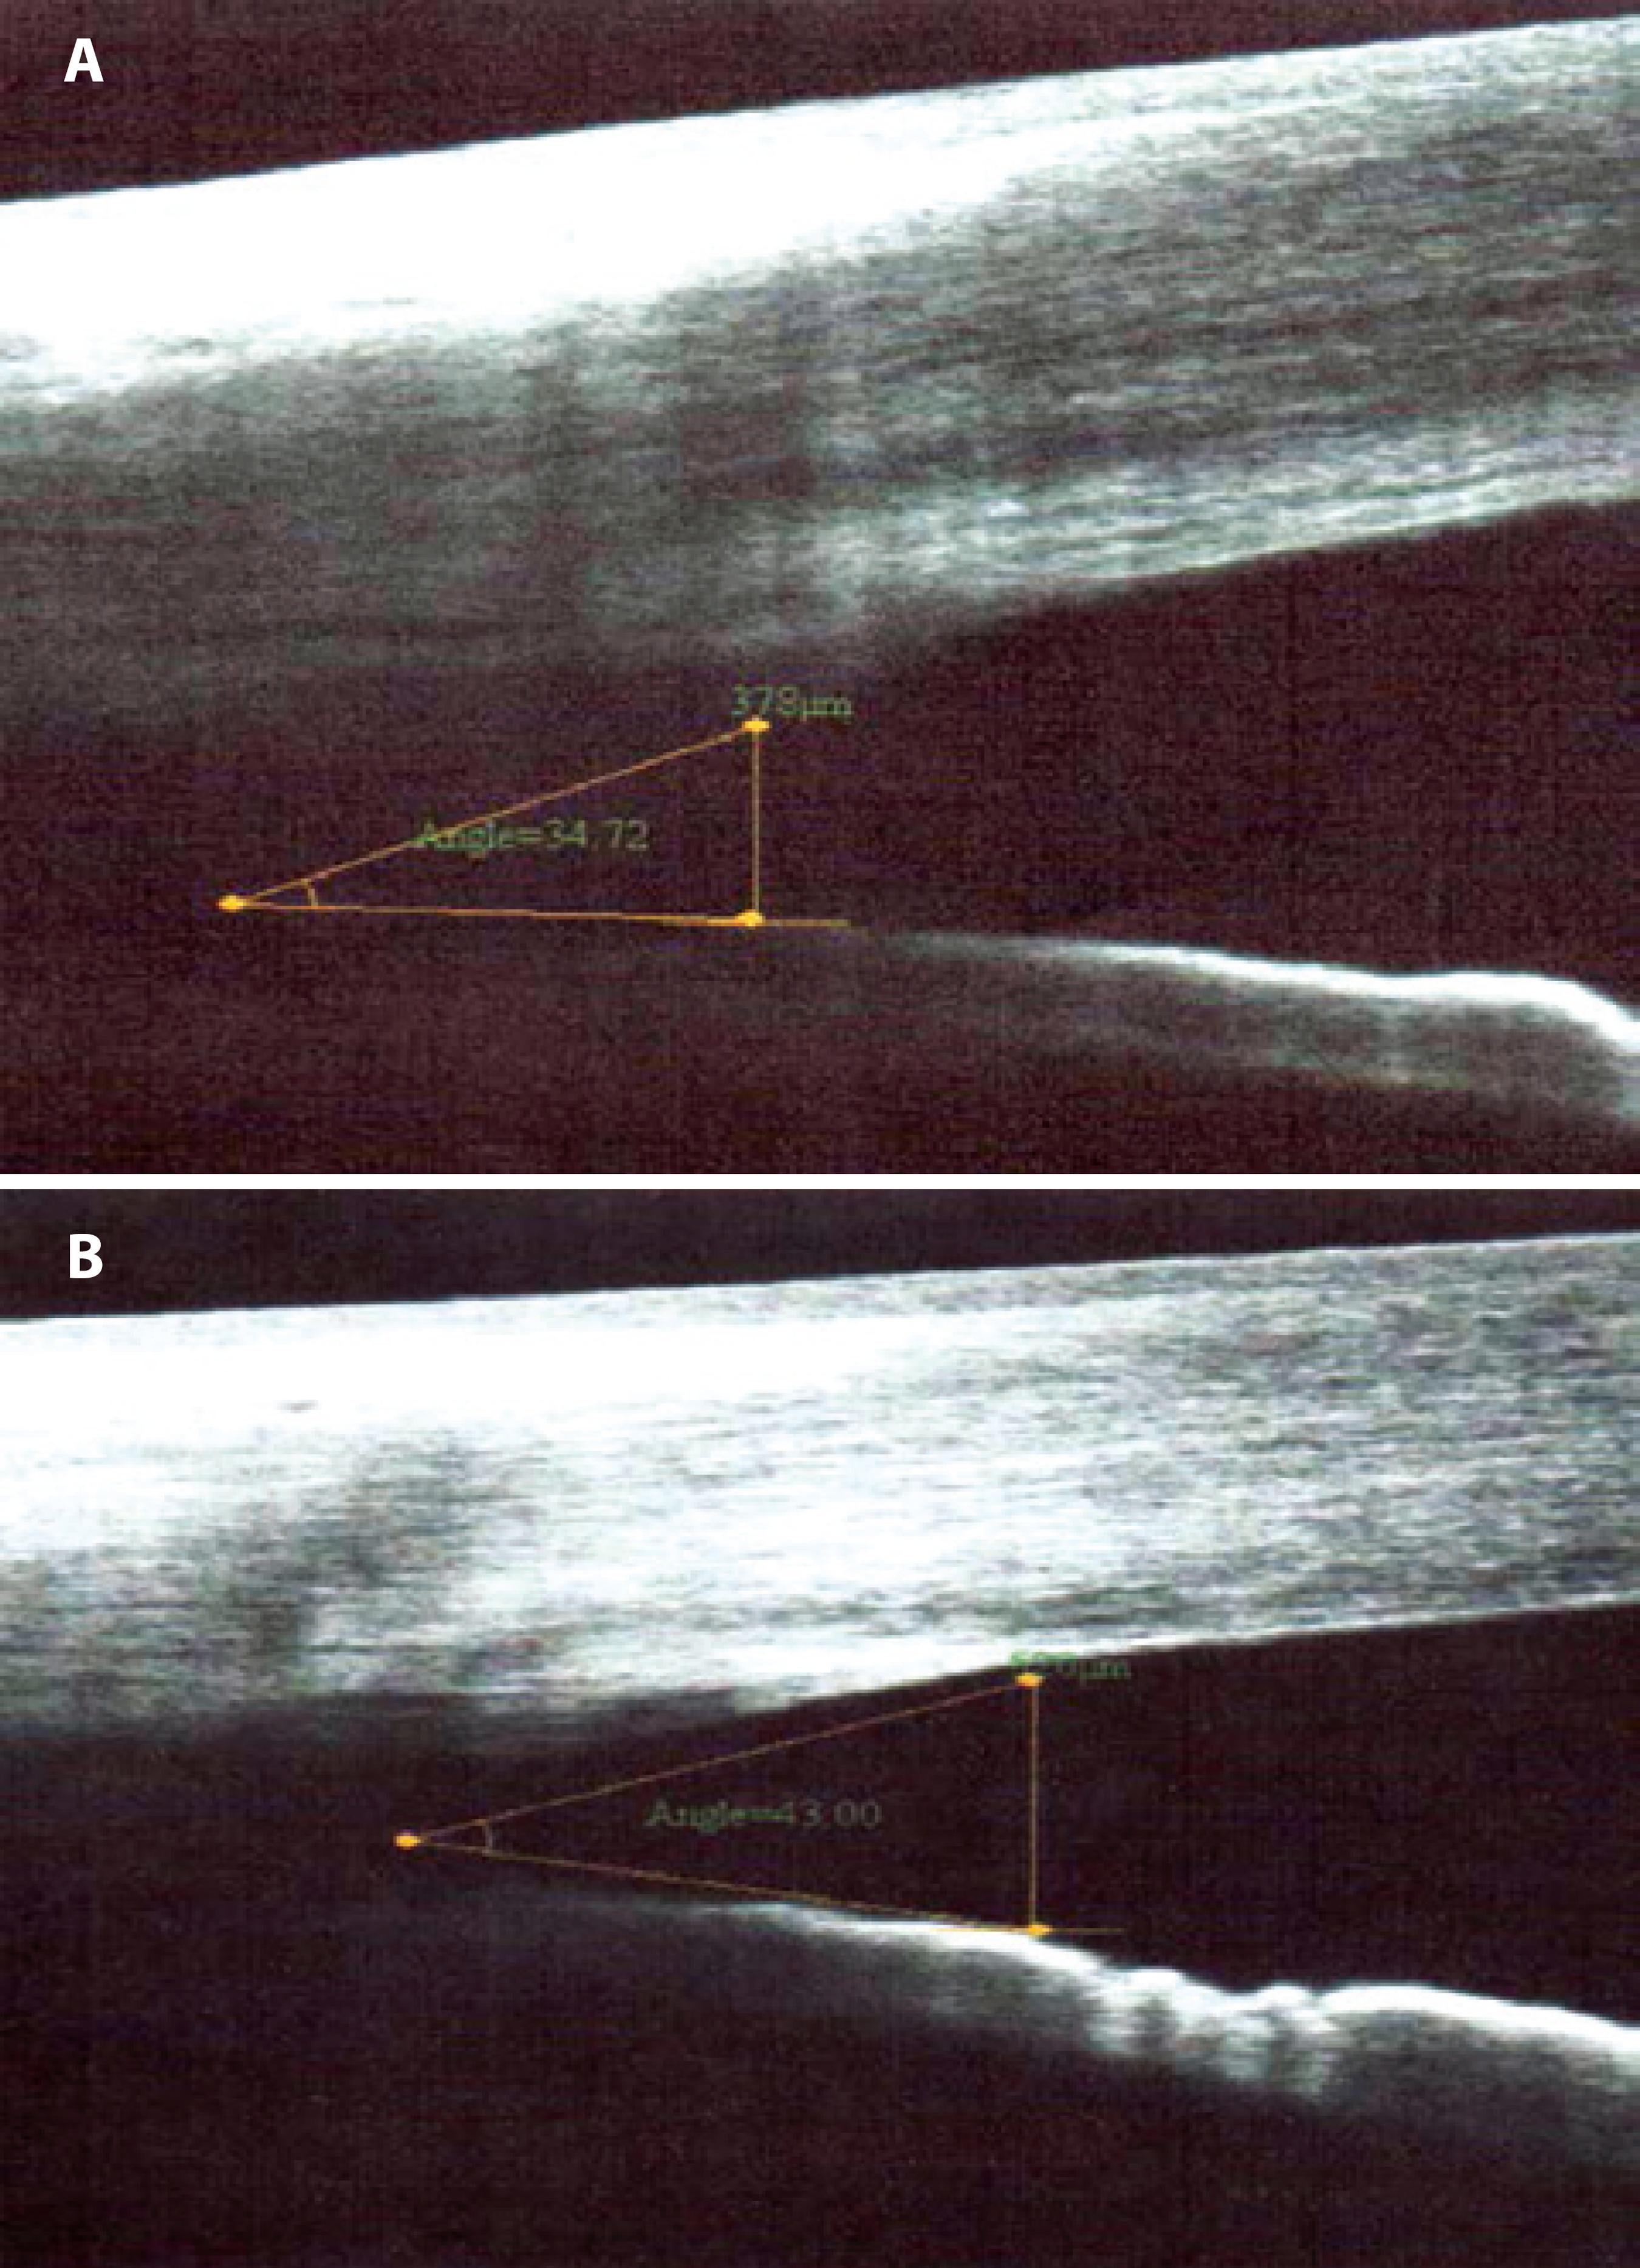

The mean AC angles of participants was 44.3° ± 14.4° and the mean intraocular pressure was 10.8 ± 4.5 mmHg before treatment. After treatment, the mean AC angle were 44.7° ± 14.7° and the mean intraocular pressure was 12.3 ± 3.0 mmHg (Figure 2). Tonometry values were not obtained for two patients because of their difficulty in participating in the study. No patient had IOP of >21 mmHg. The values of AC angle and IOP between the assessed periods were not significantly different (p=0.9343 and 0.1874, respectively) (Table 2).

Figure 2 A) Temporal portion of the AC angle viewed on SA-OC before the start of the treatment. B) Temporal portion of AC 15 days after the start of the treatment.